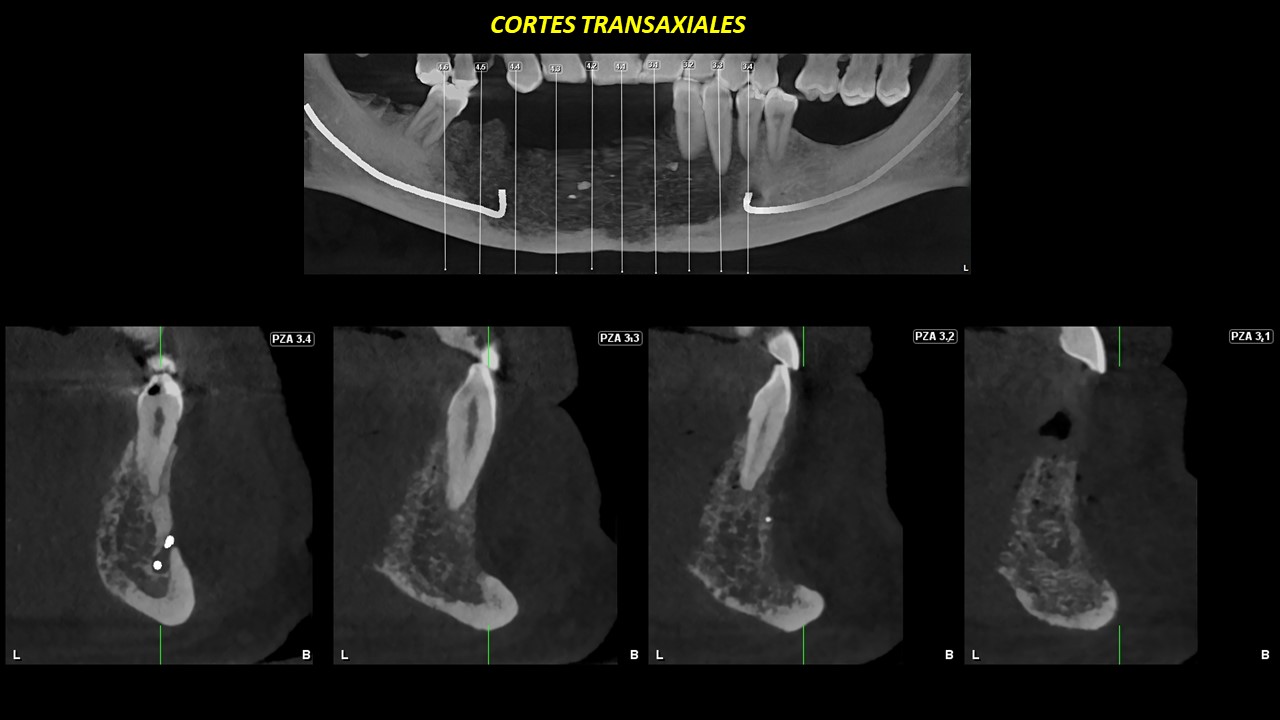

Figura 5

Figura 6

En la reformación panorámica y cortes transaxiales (Figura 5 y 6) se aprecia la extensión mesio-distal de zona de pieza 34 a zona mesial de pieza 46 y en sentido cefálico caudal de cima de procesos alveolares al reborde basal mandibular; presencia de alteración de los lechos alveolares y de restos de material restaurador a nivel de la tabla ósea vestibular.